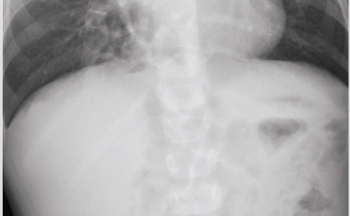

A previously healthy 4-year-old male, born late preterm by urgent cesarean delivery with an uncomplicated postnatal course, presents to the outpatient clinic for a chief complaint of worsening cough over the past 5 months. He denies current fever, rhinorrhea, shortness of breath, diarrhea, or vomiting. His cough has been worsening in severity and frequency, and mostly occurs during the daytime.

Published: January 14th 2021 | Updated:

Published: November 1st 2018 | Updated: